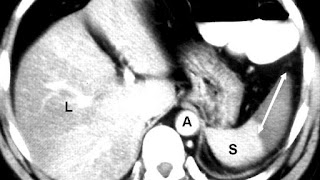

An abdominal CT scan is the most commonly used modality to confirm the diagnosis, although abdominal ultrasound can also contribute.